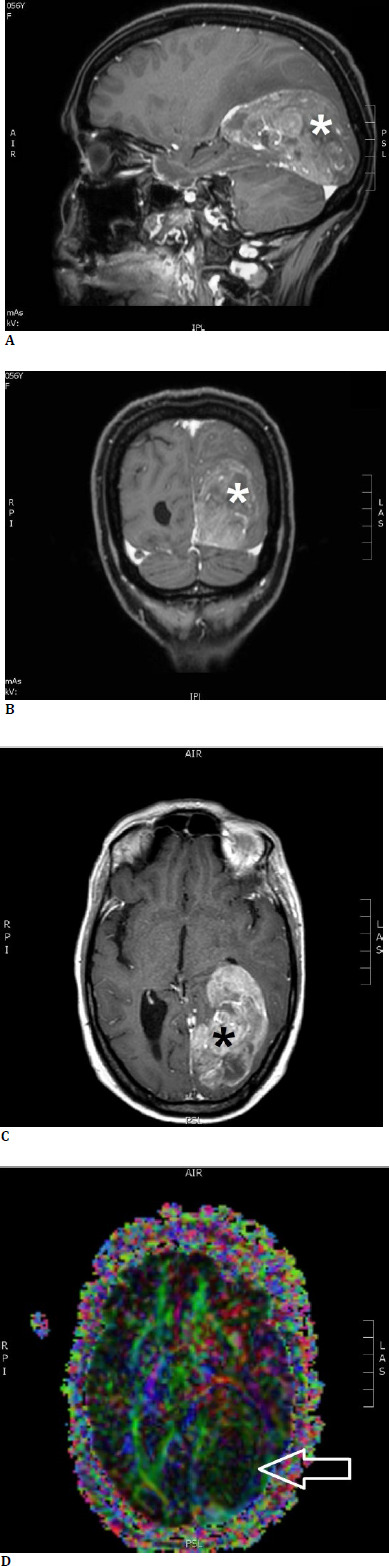

Objective: Intraoperative neuromonitoring (IONM) is nowadays a gold standard during brain tumor resections, but visual function mapping is less frequently performed in clinical practice. This article aims to report two transcortical brain tumor surgery cases affecting optic radiation, where the application of intraoperative visual evoked potentials (VEP) combined with tractography was beneficial to protect the patients' vision.

Methods: Two patients with brain tumors compressing the left posterior visual pathways underwent surgery under general anesthesia using IONM and VEP with neurologic improvement and preservation of vision.

Results: VEP is beneficial in the surgery of intra-axial lesions affecting the posterior visual pathways (optic radiation, visual cortex) and parasellar lesions involving the anterior visual pathways (chiasm). They can also be effectively combined with other mapping methods such as tractography.

Conclusions: According to our experience, IONM with VEPs and neuronavigation with tractography protect visual function in transcortical approaches to resecting tumors near the optic radiation and should be considered a standard monitoring method for such operations.